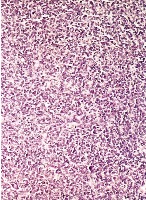

This is an AI laboratory project by Linette Dannah Cartagena, a second year medical student. Ovarian cancer can be classified into four main types: epithelial tumors, germ cell tumors, stromal tumors, and small cell carcinoma of the ovary. This model aims to recognize each type through AI. All one has to do is to simply by upload a photo of the histological slide.